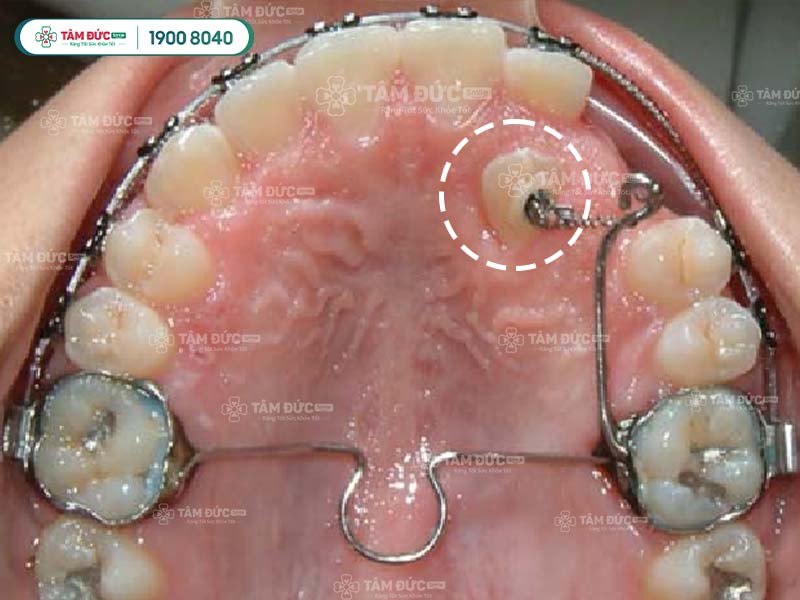

5.2. Giai đoạn 2: Phẫu thuật bộc lộ răng

Nếu răng ngầm nằm sâu trong xương hàm, bác sĩ cần thực hiện phẫu thuật bộc lộ răng để lộ phần thân răng ra ngoài. Phẫu thuật này được thực hiện dưới gây tê tại chỗ, nên sẽ không cảm thấy đau đớn.

5.3. Giai đoạn 3: Kéo răng

Sau khi răng đã được bộc lộ, bác sĩ sẽ sử dụng hệ thống lực kéo để di chuyển răng lên trên cung hàm. Có 3 loại hệ thống lực kéo chính: